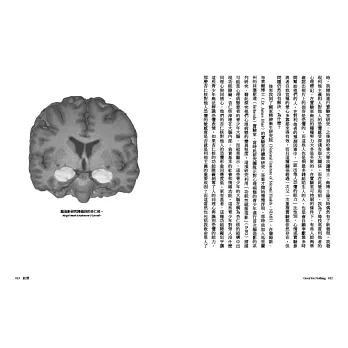

知名社會神經學家艾比蓋爾.馬許(Abigail Marsh)利用「功能性磁振造影」(fMRI)仔細研究那些惡極和良善的大腦,從連家人都畏懼的有心理病態特徵的孩童到捐腎給陌生人的無私利他成人,以突破性的科學發現告訴我們,答案就在大腦對他人恐懼情緒的反應。大腦杏仁核做為我們多數人「善」的硬體裝置,它的變化能說明英雄或病態行為。